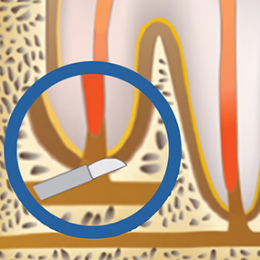

STEP 03

염증 조직을 제거한 후,

오염된 치아 뿌리 끝을

삭제합니다.

STEP 04

뿌리 끝에 MTA

(Mineral Trioxide Aggregate)

충전 후 마무리해줍니다.